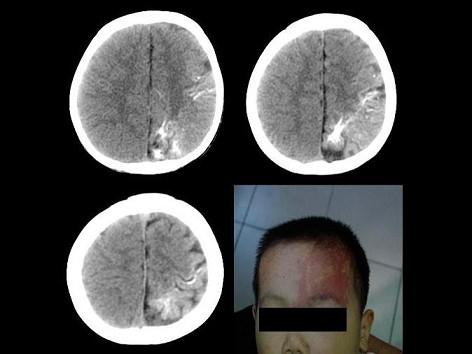

问题 男,8岁,出生9个月后常出现发作性癫痫,查体:右侧肢体轻度萎缩,肌力Ⅳ级,肌张力增高。结合所示图像,最可能的诊断为?(?)

选项 A.脑出血 B.Sturge-Weber综合征 C.结节性硬化 D.脑膜瘤钙化 E.动静脉瘘畸形

答案 B